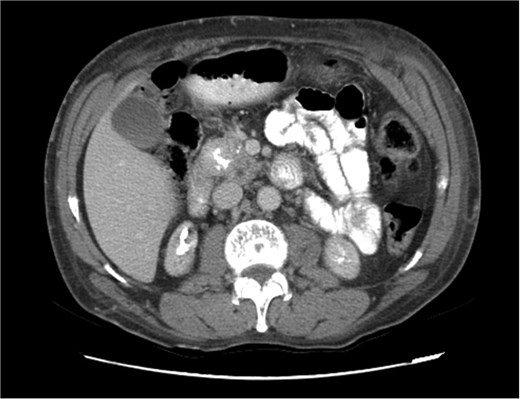

Upon admission in January 2025, the patient presented with altered mental status, dehydration, and hypoglycemia. The recurrence of hypoglycemic episodes was confirmed by laboratory studies and imaging, which identified a well-defined 3 cm mass in the pancreatic head on triphasic computed tomography (Figs 1–3). Given the diagnosis of recurrent malignant insulinoma and the possibility of resection, a surgical approach was chosen.

Triphasic computed tomography of the pancreas, portal phase, showing a tumor in the head of the pancreas.